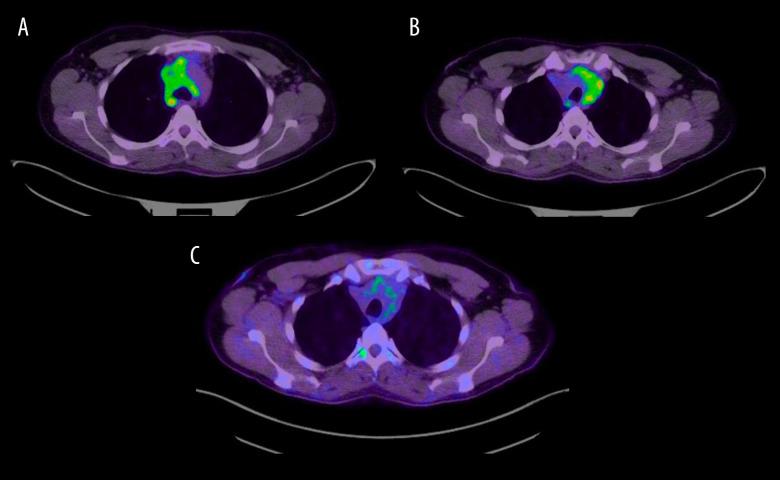

BACKGROUND Fibrosing mediastinitis is a rarely seen, progressive disease. It results from an excessive fibrotic reaction in the mediastinum. We describe a presentation of fibrosing mediastinitis that, to our knowledge, has never been seen before. CASE REPORT A 30-year-old female Colombian flight attendant presented with a right eyelid droop. Examination revealed partial right-sided ptosis and miosis but no anhidrosis. An ill-defined firm swelling was palpable at the root of the neck. Chest radiography revealed a widened mediastinum, and computerized tomography (CT) showed a right paratracheal mass without calcification extending to the thoracic inlet, encasing multiple blood vessels. All basic blood tests, magnetic resonance imaging of the head, and ultrasound Doppler of the neck vessels were normal. History and work up for infections including fungal diseases, granulomatous diseases, vasculitis, and autoimmune diseases were negative. Positron emission tomography (PET) showed significant FDG uptake in the mediastinum. Mediastinal biopsy was histologically consistent with fibrosing mediastinitis. All relevant immunohistochemistry and microbiological studies were negative. Subsequently, the patient developed signs of superior vena cava compression; this was managed by balloon angioplasty, which resulted in improvement of symptoms. However, over time, her symptoms worsened progressively, resulting in a left-sided ptosis and radiological progression of the mass on CT. She received treatment with rituximab and concomitant steroids, which yielded excellent results: the treatment led to both resolution of her symptoms and regression of the mass and its metabolic activity on PET scan. CONCLUSIONS Fibrosing mediastinitis can present with an incomplete Horner's syndrome. Treatment with rituximab and steroids shows promising results in select cases of metabolically active idiopathic fibrosing mediastinitis.

一名 30 岁的哥伦比亚空姐出现右侧眼睑下垂。检查发现右侧部分上睑下垂和瞳孔缩小,但无无汗。颈部根部可触及一界限不清的坚硬肿胀。胸部 X 线摄影显示纵隔增宽,计算机断层扫描(CT)显示右侧气管旁肿块,无钙化,延伸至胸入口,包绕多个血管。所有基本血液检查、头部磁共振成像和颈部血管超声多普勒均正常。感染史和检查(包括真菌感染、肉芽肿性疾病、血管炎和自身免疫性疾病)均为阴性。正电子发射断层扫描(PET)显示纵隔内 FDG 摄取明显。纵隔活检组织学符合纤维性纵隔炎。所有相关的免疫组织化学和微生物学研究均为阴性。随后,患者出现上腔静脉压迫的迹象,通过球囊血管成形术进行治疗,症状得到改善。然而,随着时间的推移,她的症状逐渐恶化,导致左侧上睑下垂和 CT 上肿块的影像学进展。她接受了利妥昔单抗和皮质类固醇治疗,效果非常好:治疗不仅缓解了她的症状,还使肿块及其代谢活性在 PET 扫描上消退。